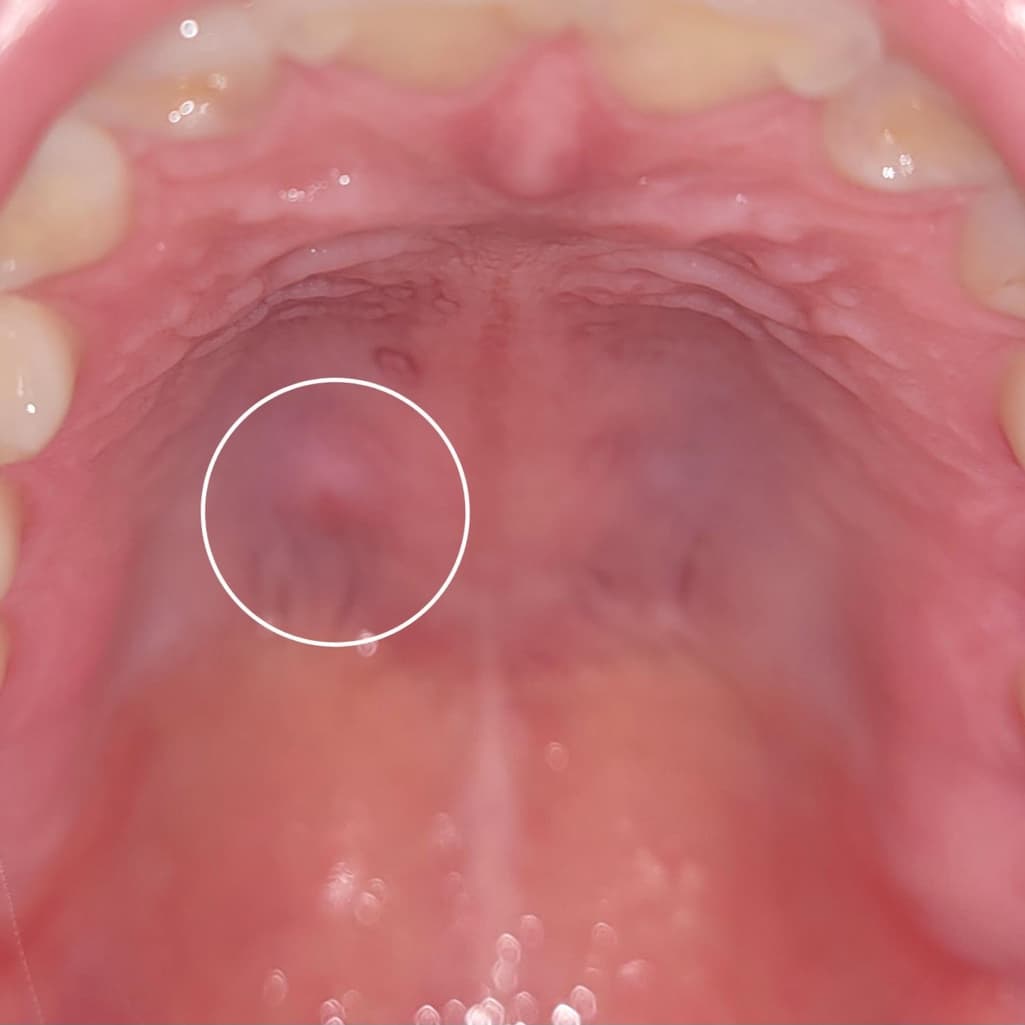

입천장에 볼록한 혹이 생겼어요 거슬리네요

이게 뭘까요

통증은 없습니다

얼마전에 생기더니 사라지지 않고 자리를 지키는 중입니다

기다리다보면 없어질까요 아니면 진료를 한번 받아봐야핯까요

사진으로 봤을 경우에는 크게 문제가 없어 보입니다. 국왕 내에는 치조골이 밖으로 자라 나와있는 외골증 등이 있을 수 있습니다. 정확한 확인을 위해서는 치과에서 진료를 받아보는 것이 좋습니다.